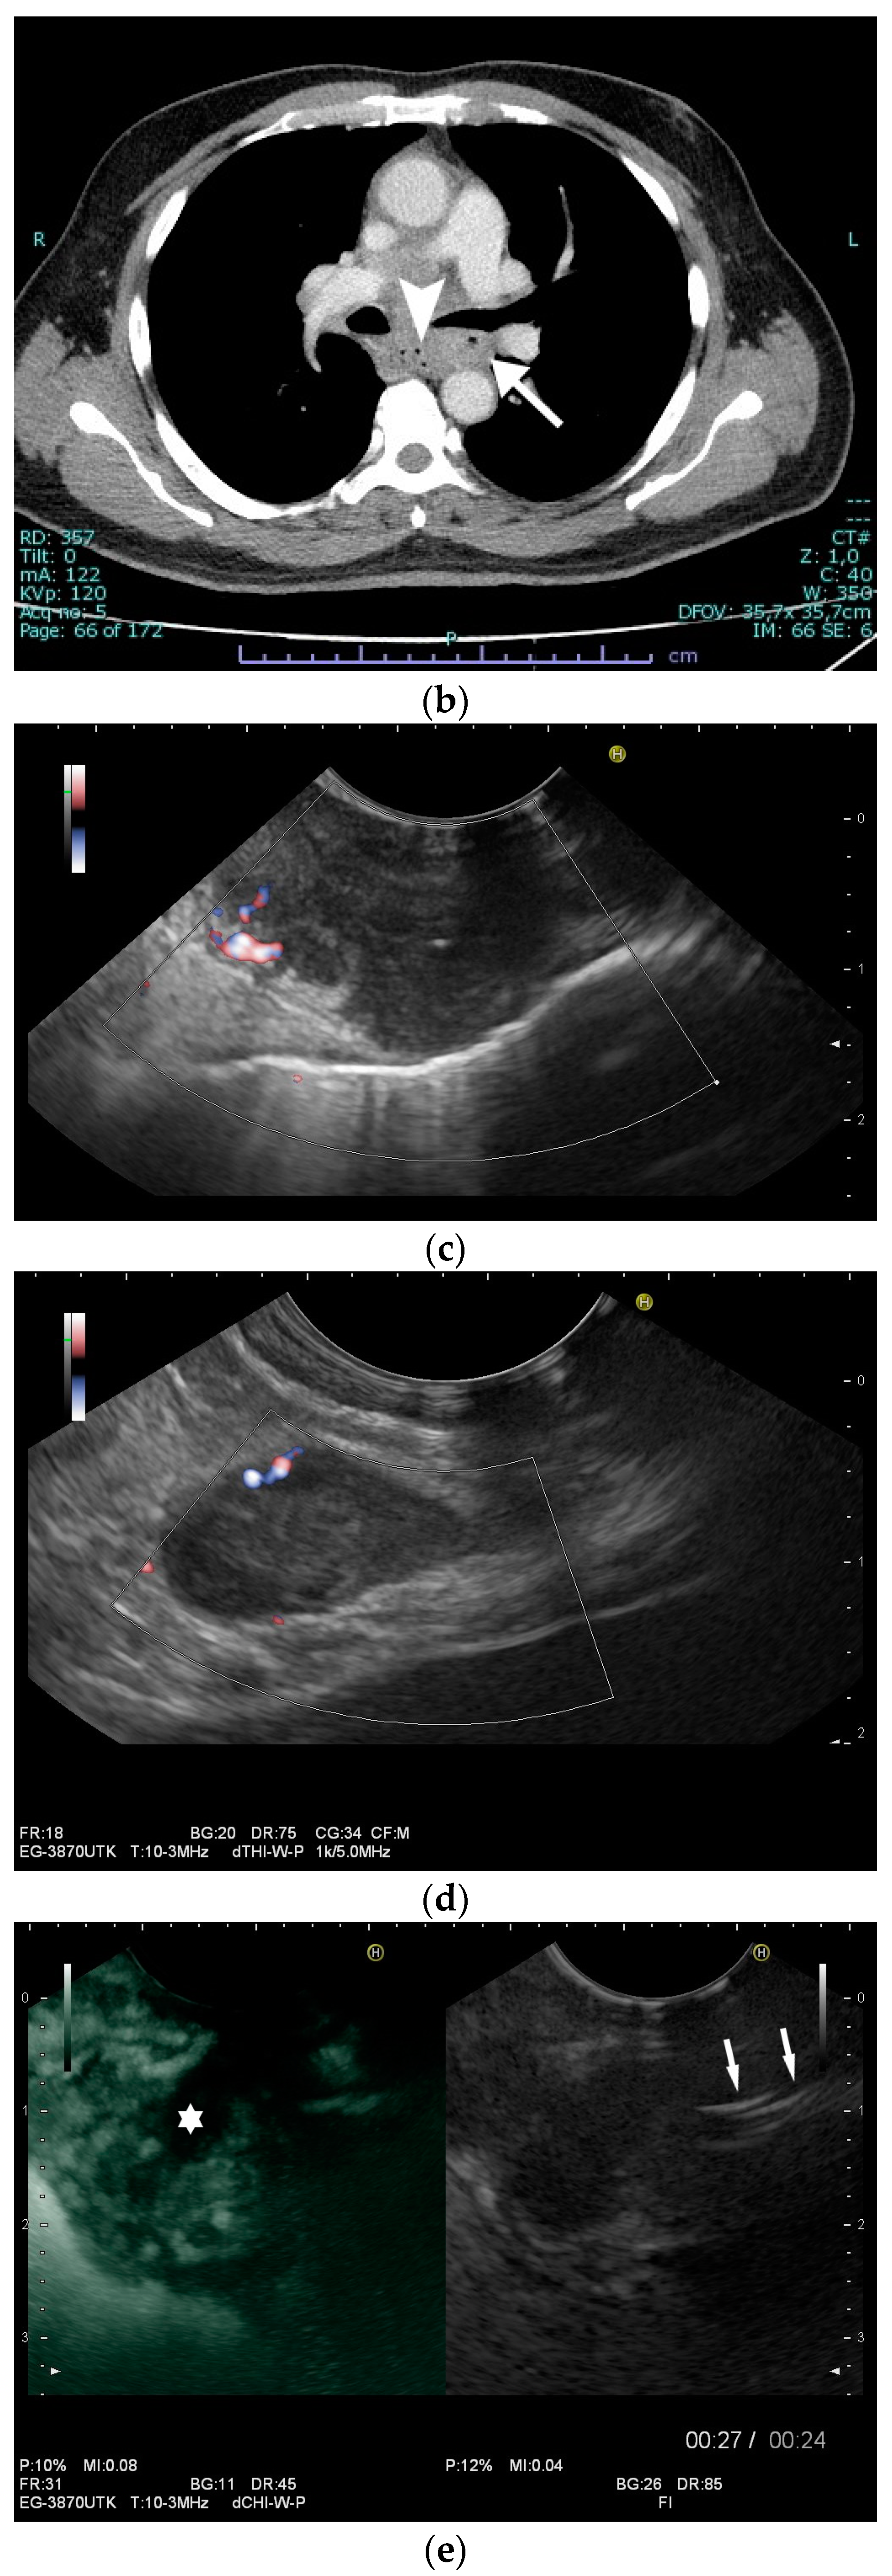

Figure 6.

A case of esophageal tuberculosis. A 52-year-old male non-smoker presented with progressive dysphagia and weight loss (15 kg in 6 months). Upper GI endoscopy revealed two subepithelial esophageal masses covered by normal mucosa (a). A CT scan showed large solid mass lesions in the mediastinum, with small gaseous inclusions (arrowhead) and a thickened esophageal wall (b, arrow). EUS ruled out a subepithelial esophageal tumor, and confirmed a large mediastinal hypoechoic mass infiltrating the esophageal wall, which was up to 12 mm thick with a complete loss of layering (c). Multiple enlarged and confluent hypoechoic lymph nodes were found throughout the mediastinum (d). Contrast-enhanced harmonic EUS showed the hyperenhancement of the mediastinal mass lesion and the thickened esophageal wall with some anechoic necrotic parts (*), and echogenic gaseous reflections (arrow; e). EUS-FNA (22 Gauge) of lymph nodes and of the thickened wall was performed (f; needle is marked with an arrowhead). Turbid fluid was aspirated from one lymph node, and then sent for cytological and microbiological examination and polymerase chain reaction (PCR) for mycobacteria. Positive Ziehl–Neelsen staining and PCR for mycobacterium tuberculosis and cheesy, necrotizing granulomas (g), cytology, Papanicolaou stain: giant cell; (h), histology, hematoxylin-eosin stain: necrotizing granulomas; courtesy Gunnar Schröder, Institute for Pathology Wildau, Germany) established the diagnosis of extrapulmonary tuberculosis involving the mediastinum and esophagus. Bronchoscopy revealed a fistula opening in the left main bronchus marked by the black arrow (i).